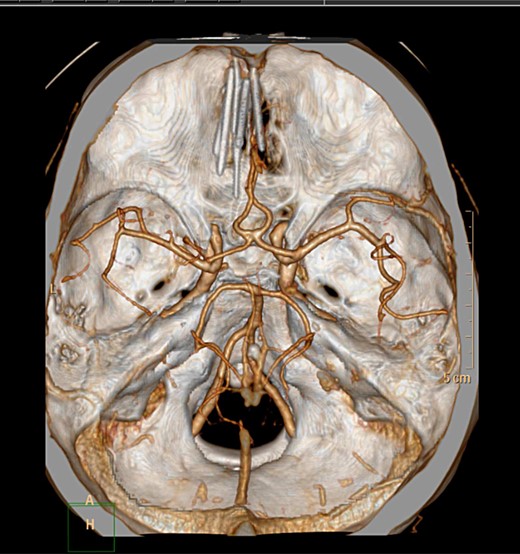

Following the current presentation, he was commenced on levetiracetam and a CT angiogram was performed to rule out an intracranial vascular injury. A preoperative CT slice and three-dimensional (3D) reconstruction of the needles in-situ is provided in Figs 1 and 2.

Axial CT 3D reconstruction showing six needles traversing intracranially and their relationship to vascular structures.